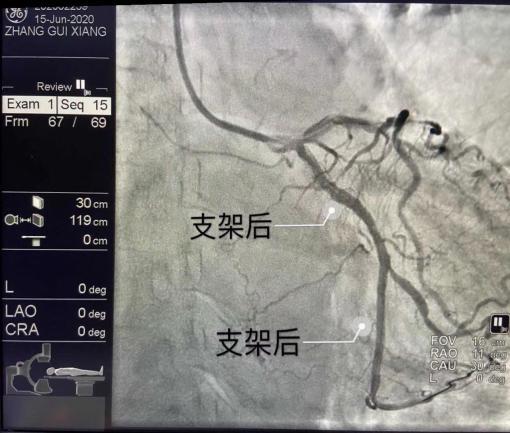

好在心内二科陈用贵团队对抢救这样的患者拥有着丰富的经验,他们在半小时内,于患者冠状动脉回旋支近段及远段共植入两枚支架,使患者症状明显缓解,术后生命体征平稳,安然返回病房。